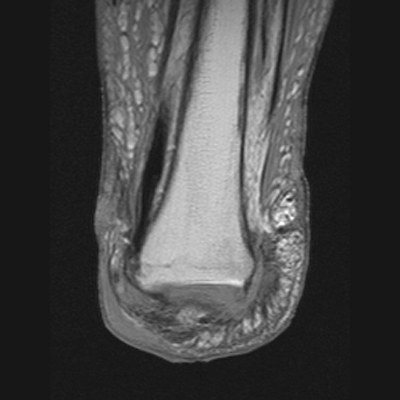

The MRI images below demonstrate the level of the Symes amputation along with bony and

soft tissue changes. Note the thick heel pad forming the majority of the distal

stump: the principle advantage of this procedure due to the more effective weight bearing.